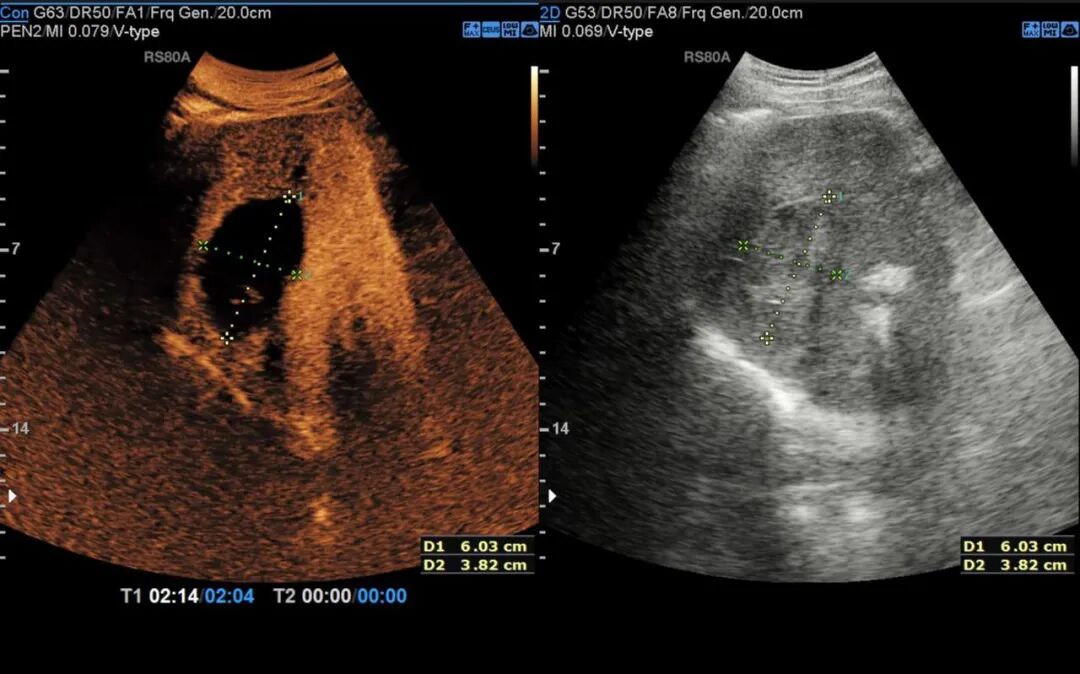

▲ 术后1月超声造影

消融完成后,术者退出电极针,经超声造影评估所有消融部位达到安全范围后手术顺利结束,术后给予对症支持治疗,患者恢复良好。术后3天超声造影显示肿瘤部位呈无血供现象,周边血管结构保存完整,消融效果良好且安全。术后1月超声造影显示病灶明显缩小,消融效果显著。